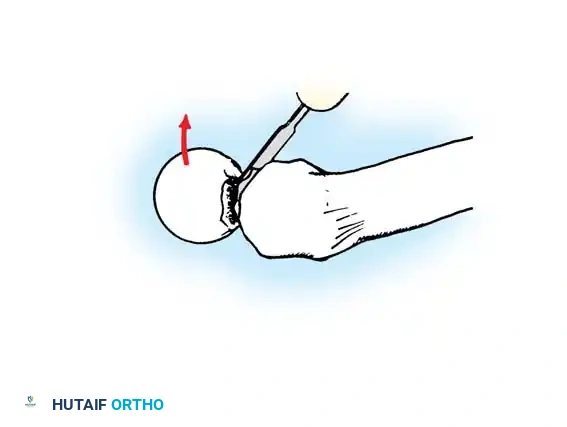

3. Guide Wire Placement

Whether using an SHS or a CMN, accurate placement of the guide wire into the femoral head is the most critical step of the operation.

Insertion of the guide wire. The wire must be positioned centrally in the femoral head on both AP and lateral views.

The Tip-Apex Distance (TAD):

Described by Baumgaertner, the TAD is the sum of the distance from the tip of the lag screw to the apex of the femoral head on both the AP and lateral radiographs. A TAD of less than 25 mm is strongly predictive of successful fixation; a TAD > 25 mm significantly increases the risk of screw cut-out.